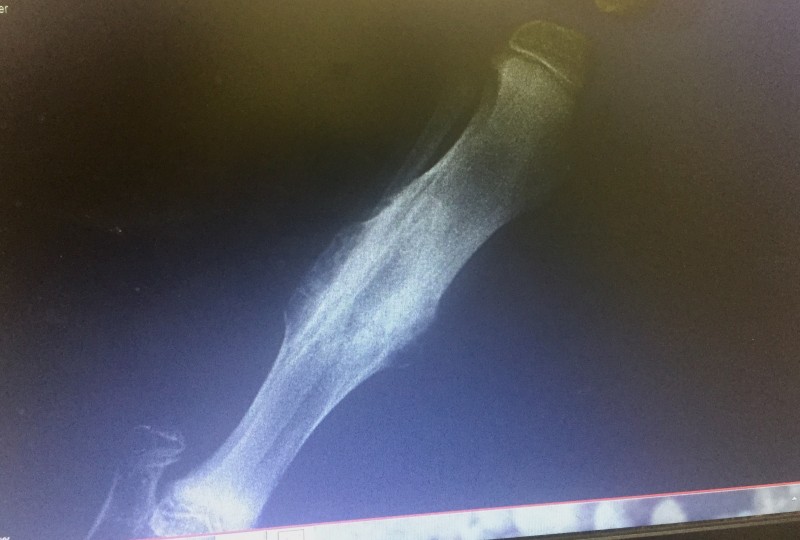

He now weighs 15.7 kgs(34.54 Pounds) and is still quite lean and we continue to work on slowly getting the muscle mass and weight on him. With his healing back broken leg, being lean is in his best interest yet we all would like to now see some more pounds put on.

His Vet was really impressed with how far that leg has come along since he was last seen and having to pull the cast off so we could focus on the ankle. Many may remember the video I took the day his latest cast came off.

I have been doing three times daily small sessions of massage, thermal therapy, ROM and flexion exercises at home and his Vet is so pleased with his progress!

He says that BHRR’s Booker’s leg is now about 80% healed and he is extremely happy with the muscle tone and symmetry between both of his back legs now.

That back leg shall never be perfect yet Dr. Liston feels that the integrity shall continue to come with strength, time and he will be as close to normal as possible!

Dr. Liston says that his healing is way ahead of where he felt he would be at this time and yay!

We still have a ways to go yet step by step we are getting there!